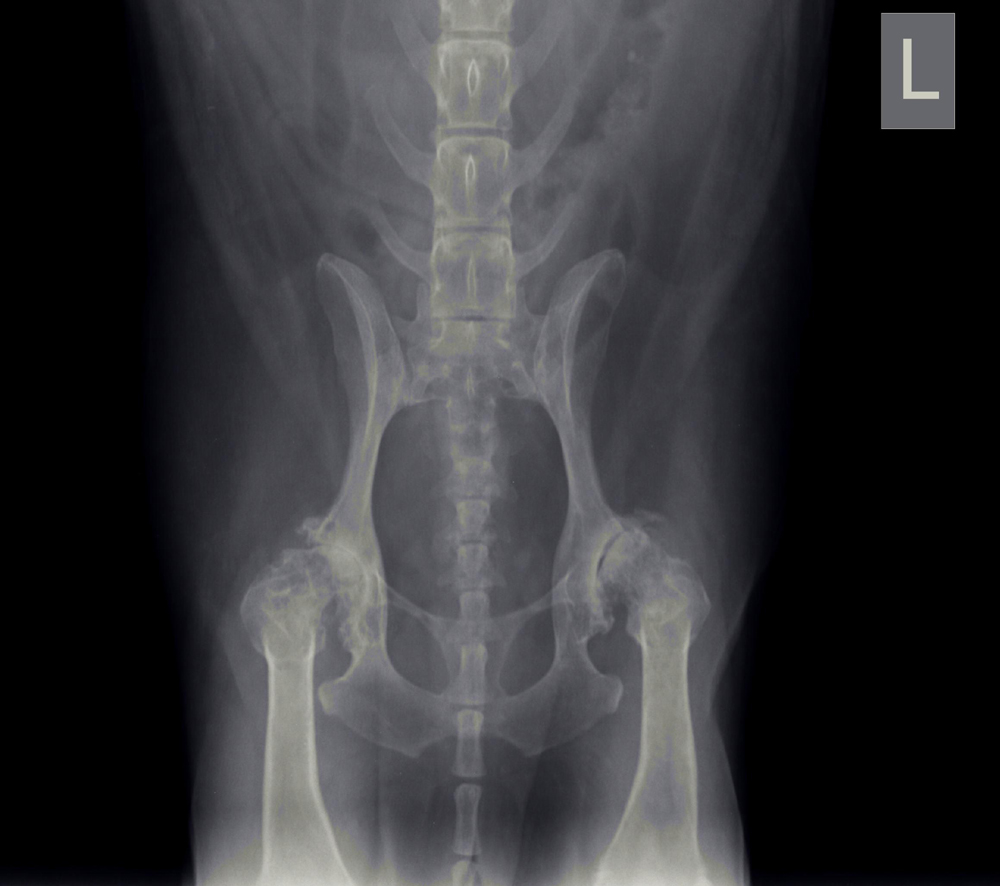

Heupdysplasie (HD)

Onder heupdysplasie wordt het volgende verstaan: een te ondiepe heupkom, waardoor de heupkop te veel ruimte heeft om te bewegen. Er is niet één enkele oorzaak voor te geven; meestal is het een combinatie van snelle groei, inspanning, voeding, leefomstandigheden en erfelijke factoren. Bij erfelijke factoren bestaat een aangeboren dysbalans tussen de spieren van het heupgewricht en de groei van bot, waardoor de heupkop niet goed in de kom wordt getrokken. Wat volgt is een abnormale ontwikkeling van het heupgewricht, wat kan leiden tot instabiliteit en daardoor irritatie van het gewrichtskapsel en het kraakbeen op de heupkop met artrose (=slijtage) als eindresultaat.

Artrose aan de heupen uit zich in het algemeen in bothaakjes aan de heupkop, verbreding van de hals van de heupkop (= de aansluiting van de heupkop met de rest van het dijbeen), onregelmatigheden in het bot van de heupkom en luxatie van de heupkop ten opzichte van de heupkom (heup geheel of gedeeltelijk uit de kom).

Met behulp van röntgenfoto’s kan de diagnose worden gesteld.